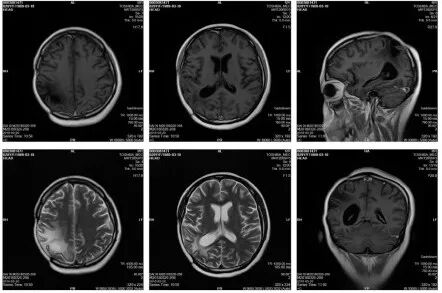

图1. 第一次术前MRI图像(2017.1.11)

图2. 第一次术后颅脑MRI图像(2017.1.22)